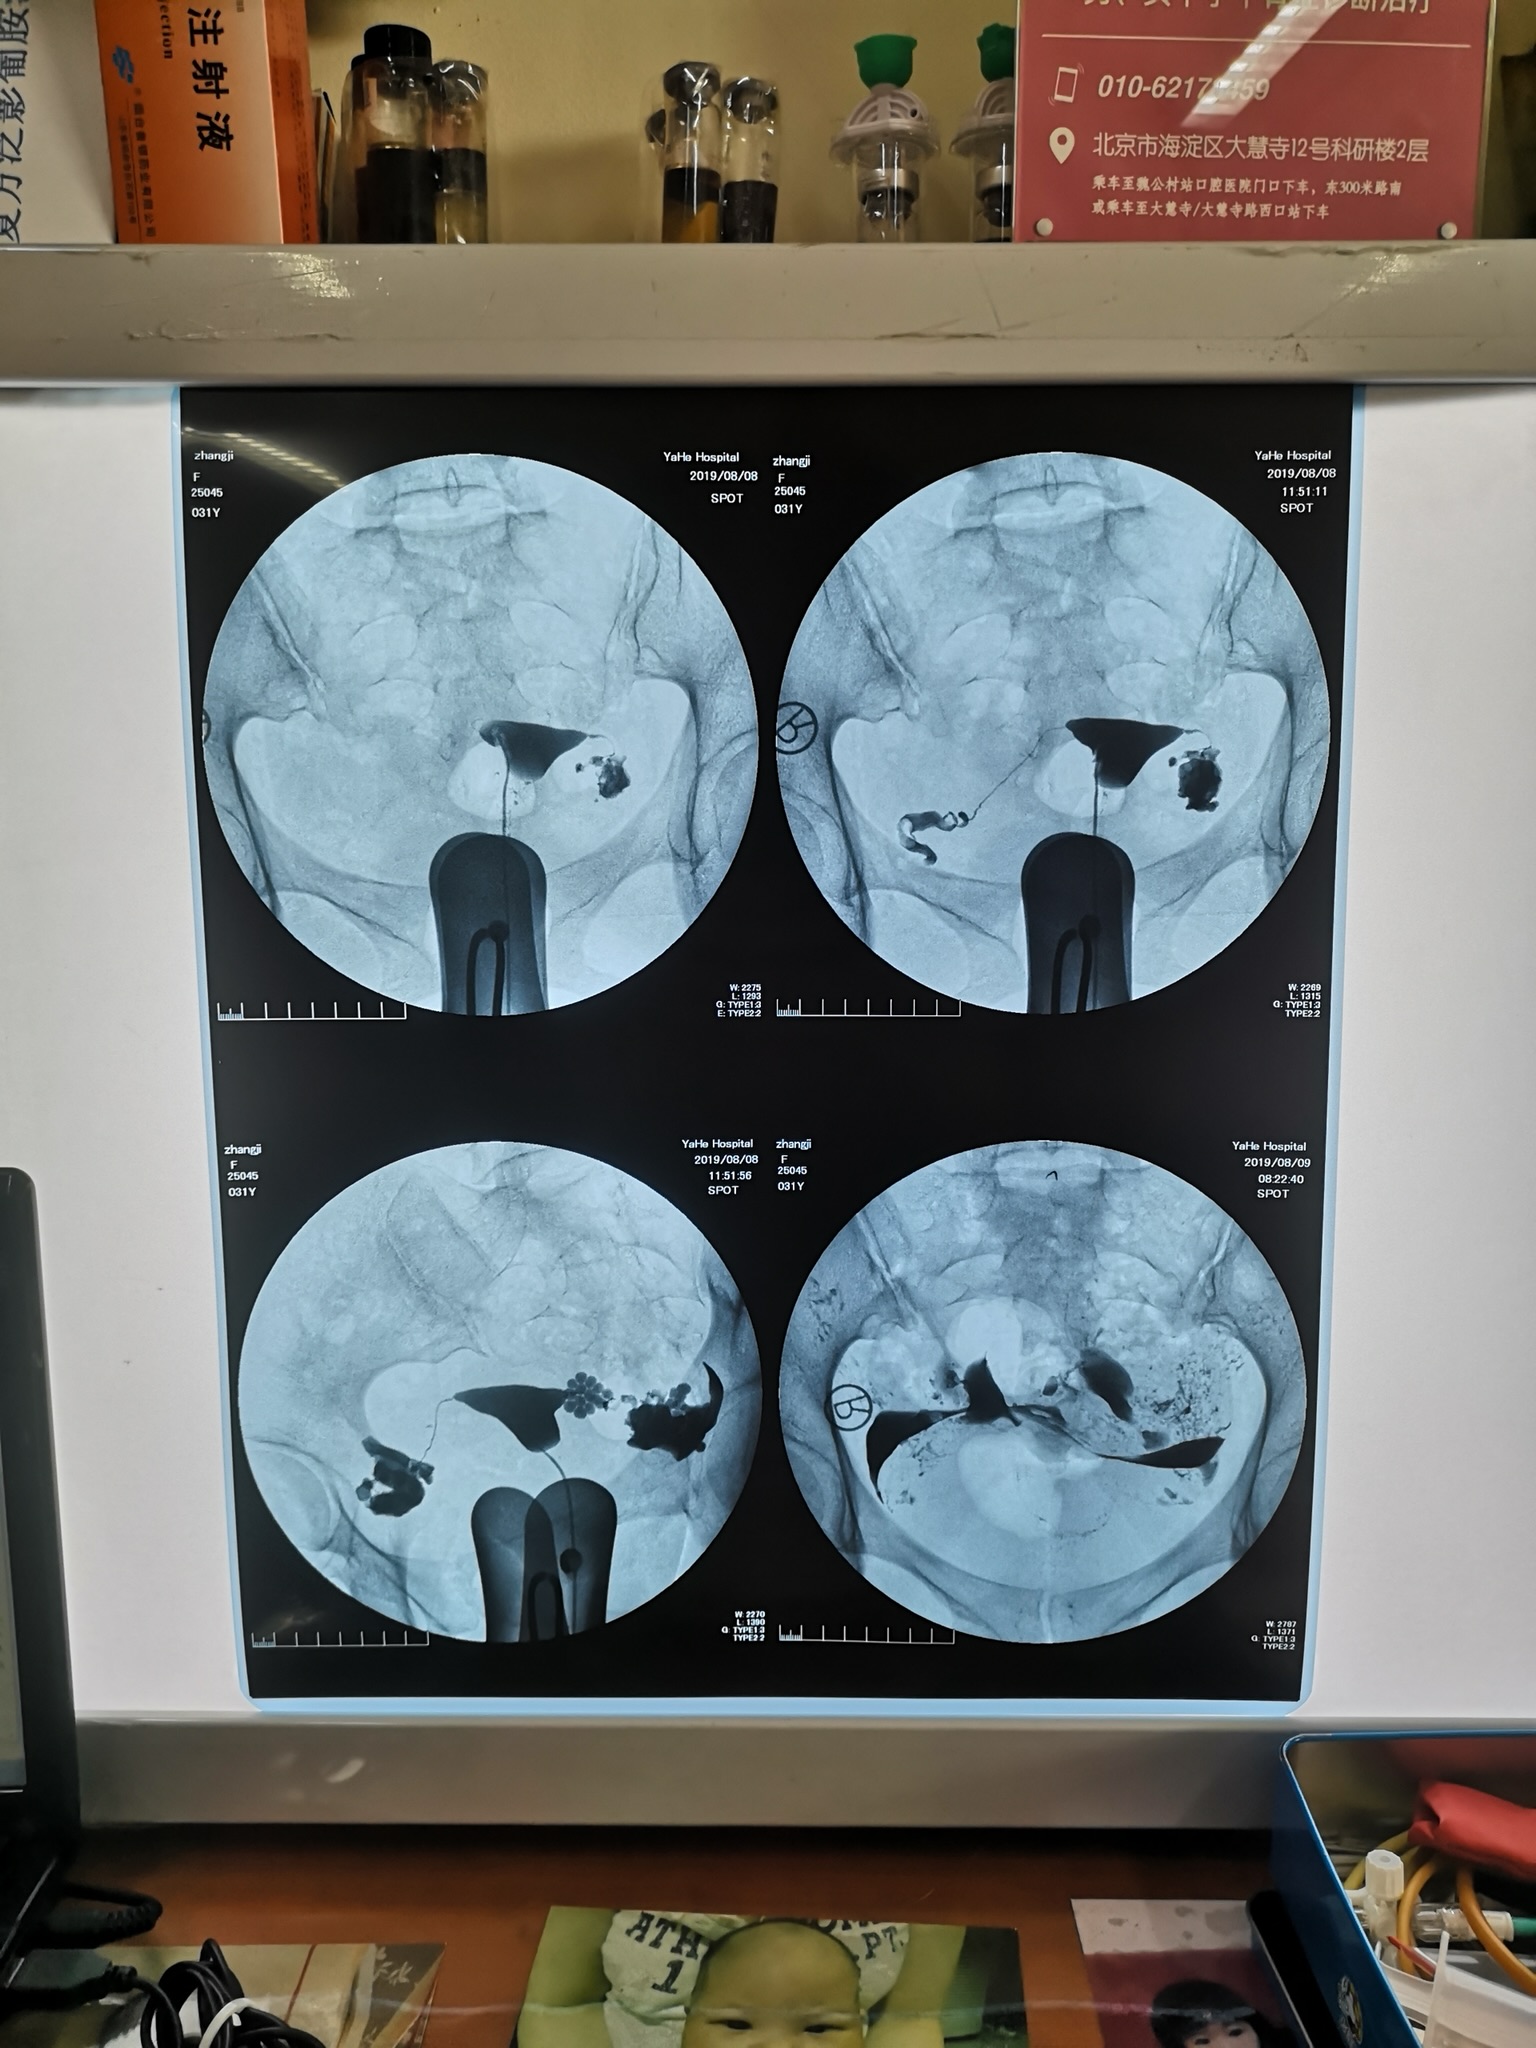

今年31岁,做过宫腹腔联合镜,两侧都有积水,

今年31岁,做过宫腹腔联合镜,两侧都有积水,术中处理了积水 也做了造口整形,半年后又去复查了输卵管造影,又过去了半年还是没怀上,是不是我该去做试管了?手术做了一年了我需要再去做二次手术吗?需要结扎或者切除输卵管吗?